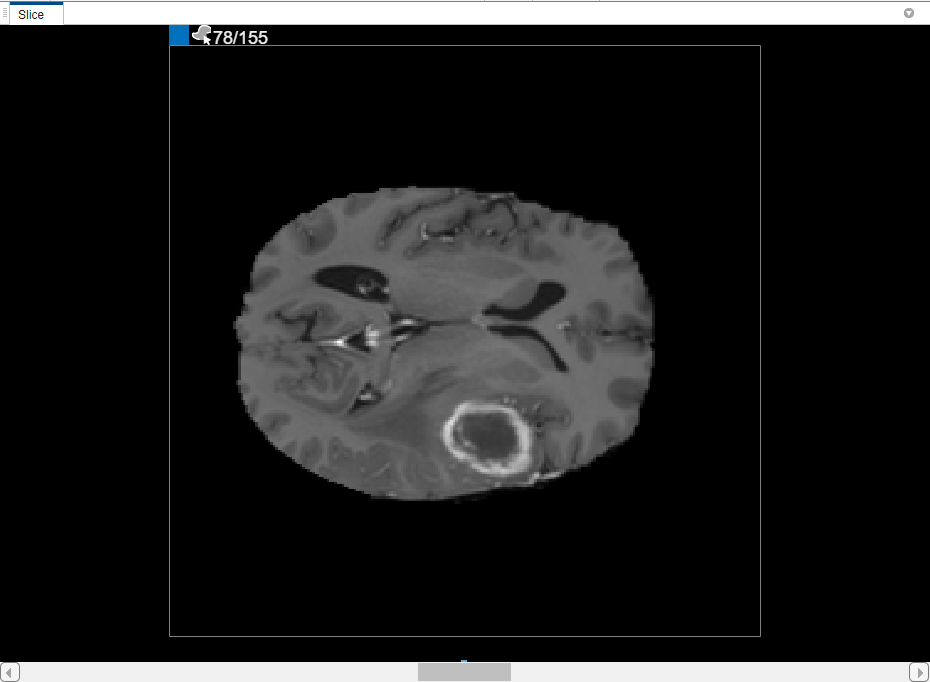

The Volume Segmenter app displays a 3-D representation of the volume in the 3-D Display pane and displays individual slices of the data set in the Slice pane.

By default, the Slice pane displays the first slice of your data. The app displays the number of the slice displayed at the top of the image, for example, 1/155. In this data set, the first few slices do not contain images of the brain.

You can also view each slice of the volume in the Slice pane. Use the slider at the bottom of the pane to move from slice to slice. You can see the tumor on slice 35 through slice 88. By default, the Slice pane displays the volume oriented along the X-Y axis, but you can change this using buttons in the Orientation section of the toolstrip on the Segmenter tab. The Slice pane is also where you use drawing tools to define the mask.